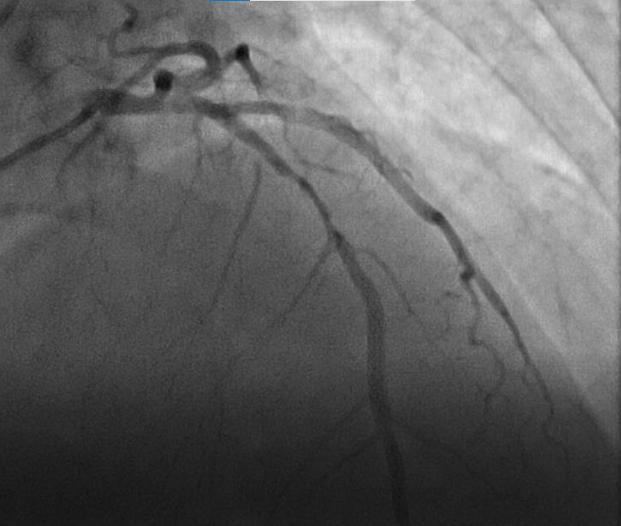

静脉溶栓后1小时,患者的胸痛明显缓解,心电图抬高的ST段回落;90分钟左右患者未再诉胸痛,心电图抬高的ST段回落超过50%,出现了频发室性早搏,考虑心肌再灌注后的心律失常,查电解质示低钾血症,予以静脉补钾后患者心律失常消失,提示静脉溶栓成功。度过关键期后,患者于6月12日顺利转入上级医疗机构行支架置入治疗。

通过溶栓治疗,让患者成功逃离了死神的追捕,获得了新生。这是贾家医院于5月27日正式启动基层胸痛中心建设后,来院的首例胸痛患者并顺利抢救成功,这标志着贾家医院的胸痛中心工作向专业化、规范化、标准化迈进,从而更好地服务片区群众。(彭世彬)